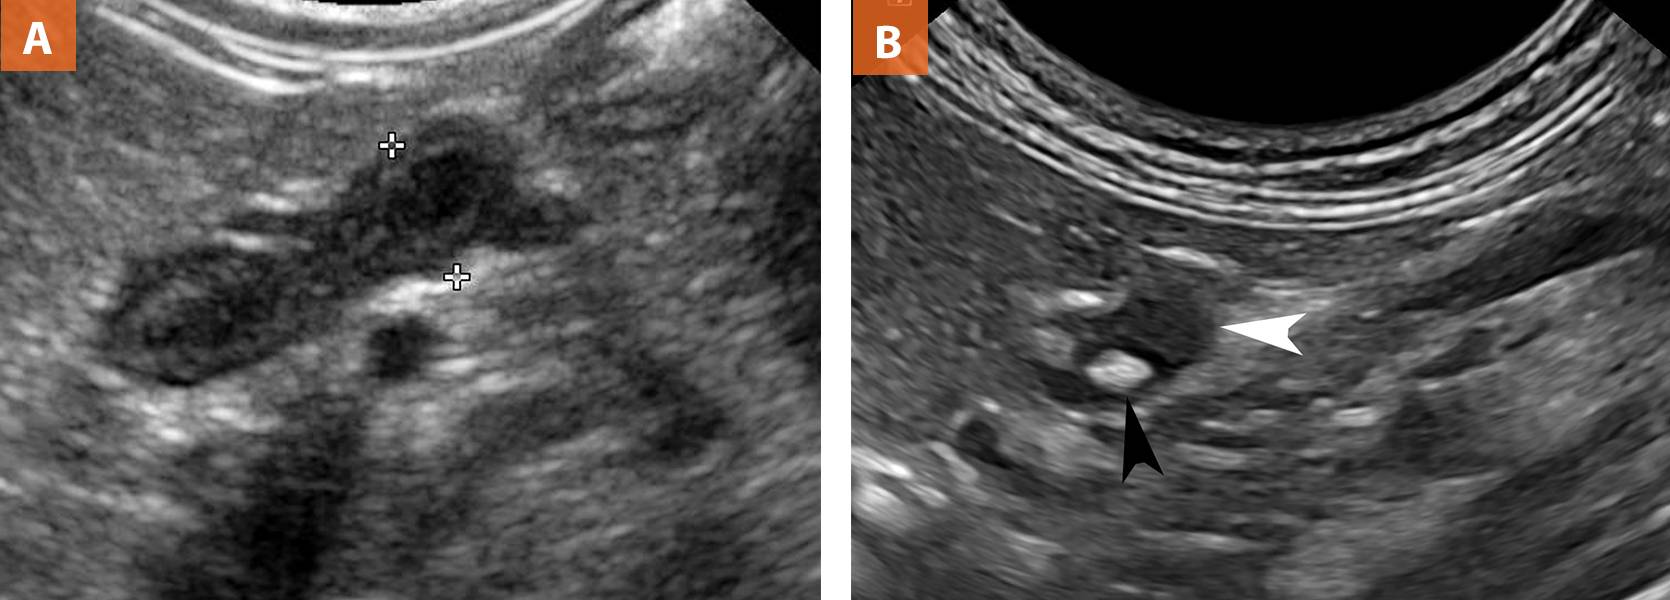

Рисунок 11. (A) Левый надпочечник собаки в продольном сканировании

Обратите внимание на форму арахиса и четкую КМД. В ближнем поле видна гипоэхогенная френикоабдоминальная вена между краниальным и каудальным полюсами железы

Анэхогенная структура в дальнем поле – прилежащая краниальная мезентериальная артерия. (B) Продольный скан надпочечника кошки (белая стрелка). Обратите внимание на овальную форму и гиперэхогенный очаг в центре (черная стрелка), представляющий собой минерализацию. Минерализация в надпочечниках собак наблюдается при неопластических поражениях.